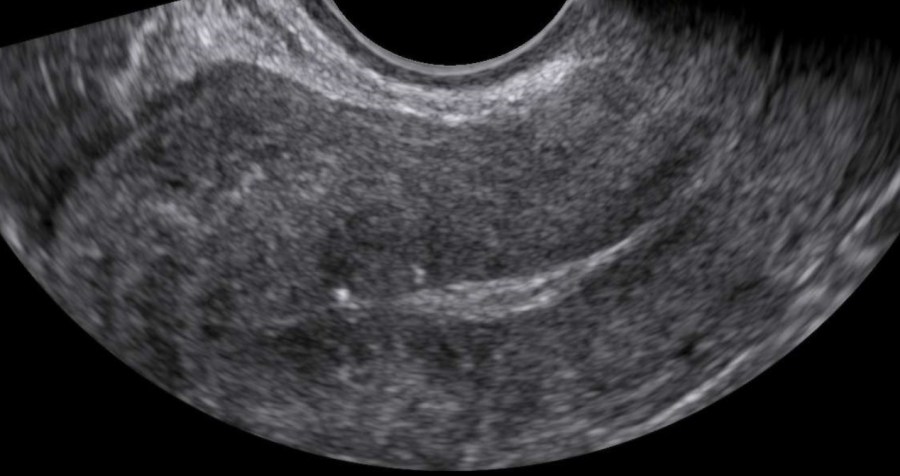

HomeGynecology Gynecology Vaginal Inclusion Cyst Laparotomy for Giant Ovarian Tumor Fallopian Tube Torsion Vesicovaginal fistula after hysterectomy Parasitic Myoma Smooth Muscle Tumor of Uncertain Malignant Potential (STUMP) Mucinous Cystadenoma Hysteroscopic Myomectomy Laparoscopic Excision of a Mesothelial Cyst of the Uterus Laparoscopic Treatment of A Chronic Ectopic Pregnancy Laparoscopic Removal of an intraabdominal IUD Paraovarian / Paratubal Cyst LAparoscopic Supracervical Hysterectomy (LASH) Laparoscopic Myomectomy Laparoscopic Management of Tubal Ectopic Pregnancy #2 Salpingectomy Laparoscopic Management of Tubal Ectopic Pregnancy #1 Salpingotomy Masterclass – Ultrasound Study of the Tubal Ectopic Pregnancy Total Laparoscopic Hysterectomy (TLH) Laparoscopic Management of an Immature Teratoma Ultrasound Study of Borderline Ovarian Tumors Laparoscopic Bilateral Salpingectomy: Tips & Tricks Transcervical Resection of the Endometrium Ultrasound Study of Cervical Cancer Pelvic Lymphoma Ureterovaginal fistula after hysterectomy Adenomyosis How to optimize your ultrasound image Hematometra after conization Endometrial Cancer Hemoperitoneum Endometrioma Infectious non-puerperal mastitis Hydrosalpinx Adnexal torsion Deep infiltrating endometriosis Struma ovarii Caesarean scar pregnancy Interstitial pregnancy Cervical pregnancy Share this: Share on X (Opens in new window) X Share on Facebook (Opens in new window) Facebook Share on LinkedIn (Opens in new window) LinkedIn